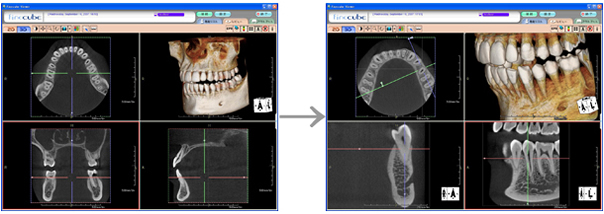

volumeをXYZ方向にそれぞれ512分割しておりこのときのスライスピッチは標準モード撮影で147㎛、高解像度モード撮影(ハイレゾ)で101㎛です。 3D画像はリアルタイムで自由に動かすことができるので骨の形態や奥行きを容易に把握できます。 さらにウィンドウレベルを操作することでさまざまな画像を簡単に得ることができます。 またインプラント治療においては下顎管やオトガイ孔、上顎洞下壁までの距離を正確に測定できるので術中も安全に治療をおこなうことができます。 |

| XYZ軸断層面(水平断、前頭断、矢状断と3DVR) |

| 高性能viewer |